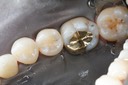

Joe Cha #29 prep